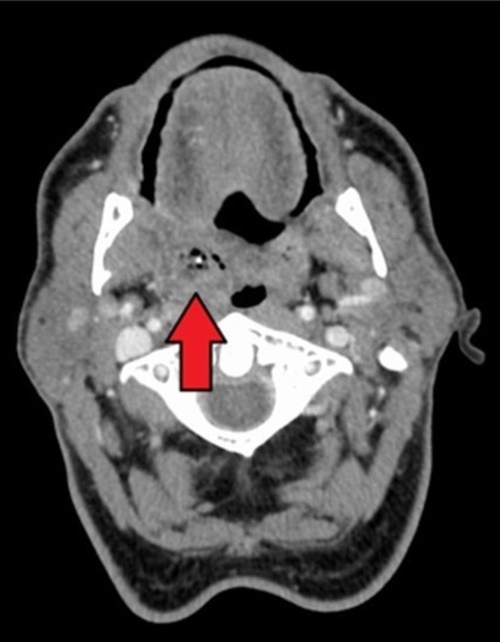

의사는 세심한 주의를 기울여 주었다.목 내시경 검사를 마치고 즉시 CT 촬영을 해보자고 했다. 나는 가슴이 철렁 내려앉았다. “목에 나쁜 것이 발견되었습니까?”라고 물었으나 주치의는 CT 결과를 보고 나서 말하자고 했다.

나는 건강한 체질이어서 난생 처음 CT를 찍어봤다. CT를 찍으면서 별의별 생각이 다 들었다. 나는 평소에 조금만 무리를 하면 목이 쉰다. ‘인터넷에서 찾아보면 목이 잠기는 건 좋지 않다던데 혹시 안 좋은 결과가 나오면 어떡하지?’하고 생각했다.

하지만 이런 마음은 사탄이 주는 것이라 생각하고 마음 편히 CT 촬영을 마쳤다. 다행히 검사 결과는 편도선 주위농양(Periton sillarabscess)으로 판명되었다. 오른쪽 편도선에 농양이 생겨서 무척 아팠던 것이다.